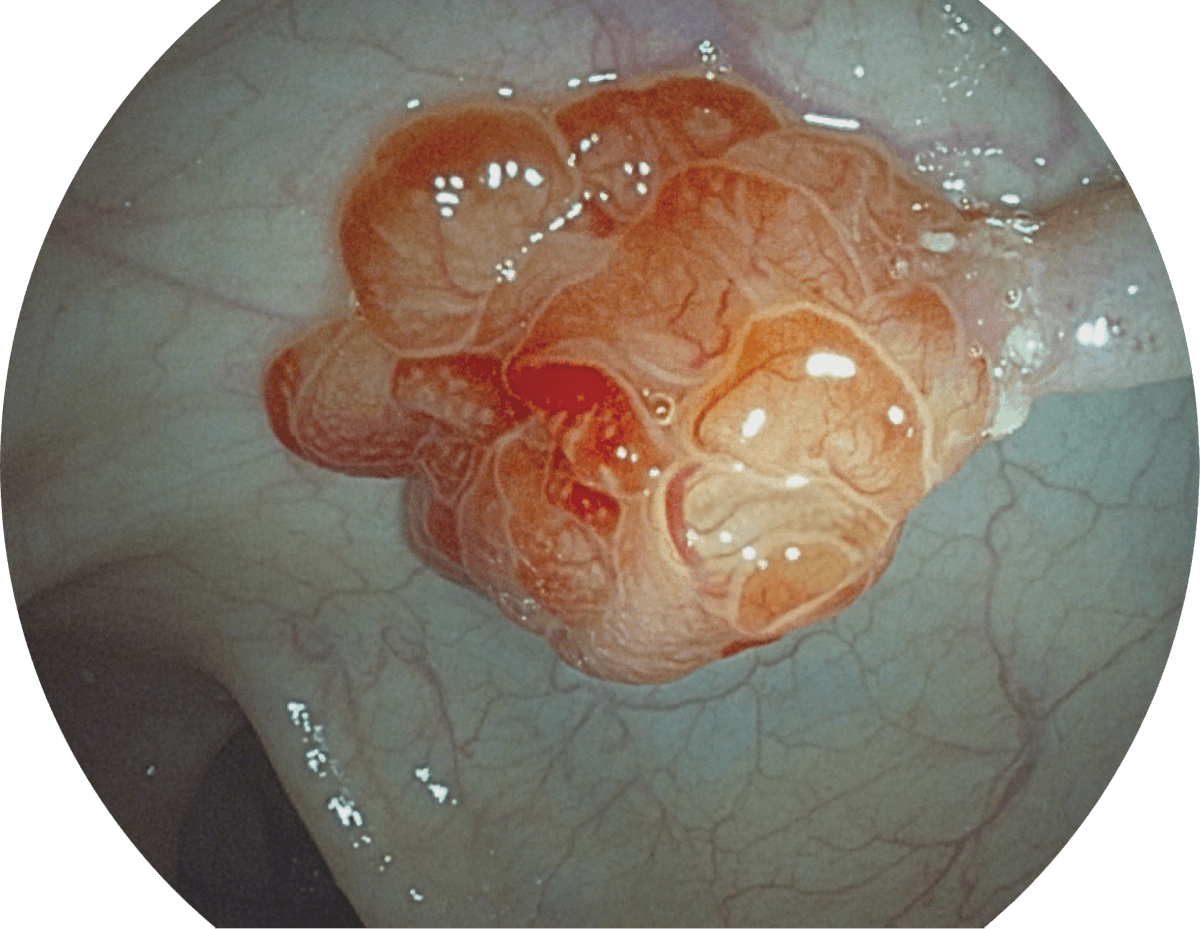

图像具有高亮度、高黏膜血管颜色对比度的特点,且不改变粘液、食物残渣、粪便的基本颜色,可在中远景下进行观察,助力消化道早期疾病的诊断。

• WL

• SFI

• VIST